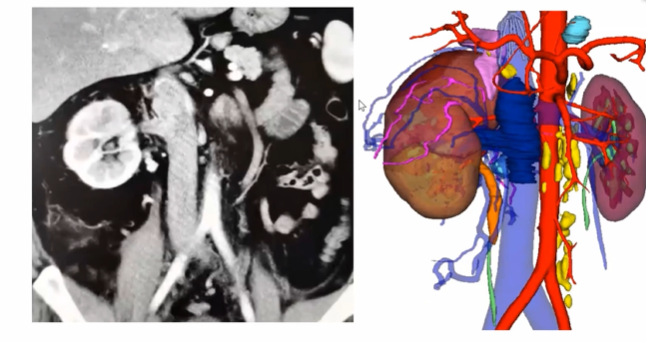

如下图所示,该病例瘤栓充满整个下腔静脉,同时长满血栓,对于该病例我们采用全封闭式的En-block切除,首先是离断下腔静脉,翻起来以后去找寻右肾动脉,切断右肾动脉以后再把左肾静脉切断,然后一直沿着瘤栓向肝后寻找游离肝门后方腔静脉。既往类似病例中肝门后方腔静脉很难暴露清楚,但是有了机器人助力,使其充分显露出来就变的相对容易很多。肝后下腔静脉经过充分游离后,再将瘤栓全部挤压进入腔静脉中,然后探查至无瘤栓处,直线切断腔静脉,将瘤栓取出。完全封闭式的瘤栓取出,可以获得很好的操作空间。该病例曾在2023年4月在第8届泌尿生殖系统研讨会上进行演示。